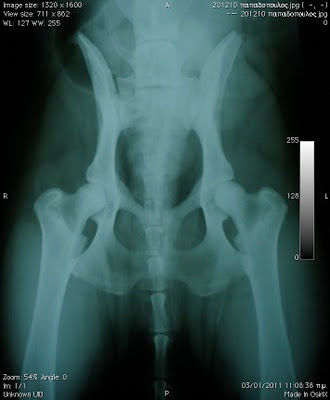

Την εξέταση του σημείου Ortolani ακολουθεί η λήψη ακτινογραφήματος των ισχίων. Για το σκοπό αυτό ο σκύλος (σε βαθιά ηρέμηση ή και υπό γενική αναισθησία) τοποθετείται σε ραχιαία θέση με τα οπίσθια άκρα σε πλήρη έκταση και ελαφρά έσω στροφή. Η συγκράτηση σε αυτή τη θέση γίνεται με τοποθέτηση αυτοκόλλητης ταινίας ιατρικής χρήσης ή με φυσική συγκράτηση από κάποιο βοηθό. Για την επίτευξη της παράλληλης θέσης των δυο μηριαίων οστών που απαιτείται, συνιστάται η τοποθέτηση ταινίας γάζας ή υφάσματος που συμπλησιάζει ελαφρά τα δυο άκρα, περιβάλλοντάς τα στο ύψος του γόνατος.

L ικόνα 1- θέση ακτινογράφησης ισχίων σε προσθιοπίσθια προβολή. Ο σκύλος τοποθετείται σε ραχιαία θέση, υποβοηθούμενος από ειδικό μαξιλάρι. τα οπίσθια άκρα φέρονται σε πλήρη έκταση με ελαφρά έσω στροφή. Ταινία γάζας ή υφάσματος στο ύψος των δυο γονάτων συμπλησιάζει τα δυο μηριαία φέροντάς τα σε παράλληλη θέση. Η απόλυτη συμμετρία του σώματος είθναι ζωτικής σημασίας για την επίτευξη συμμετρικής προβολής της λεκάνης.

εικόνα 2- ακτινογραφία ισχίων στην οποία έχουν υπολογιστεί ψηφιακά οι γωνίες Norberg

Με τον τρόπο αυτό λαμβάνουμε ακτινογραφήματα της λεκάνης τα οποία ελέγχουμε ως προς την ποιότητα αλλά κυρίως ως προς τη συμμετρία τους. Η μη συμμετρική απεικόνιση των δυο αρθρώσεων θα οδηγήσει σε λανθασμένα συμπεράσματα. Σε κάθε άρθρωση τελικά εκτιμάται η γωνία Norberg,η σφαιρικότητα της κεφαλής του μηριαίου, η θέση της κεφαλής του μηριαίου ως προς το ραχιαίο χείλος της κοτύλης, το εύρος του μεσάρθριου διαστήματος, η πάχυνση και παρουσία οστεοφύτων στο πρόσθιο προβολικό χείλος της κοτύλης, η πάχυνση και παρουσία οστεοφύτων στον αυχένα του μηριαίου και η γραμμή Morgan. Το σύνολο των παραμέτρων αυτών θα χαρακτηρίσει την ποιότητα της κάθε άρθρωσης ξεχωριστά